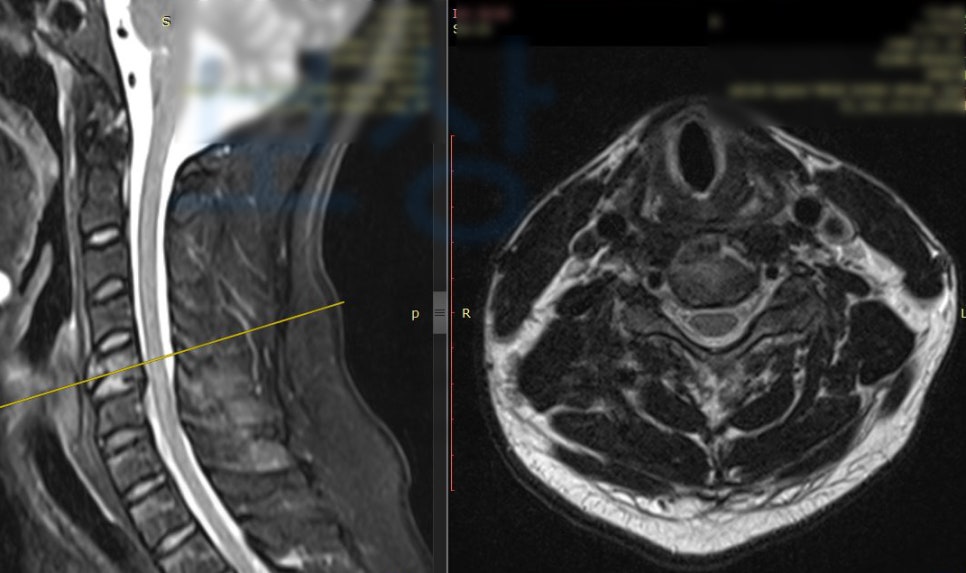

박@@님은 새벽 운전 중 차량이 미끄러지며 전복되는 사고를 당하셨습니다.

이 사고로 급하게 응급실 내원하여 정밀 검사를 실시하셨는데요,

경추골절 s12.9

을 주 진단으로 받게 되었고 흉추의 골절 s22.0 도 함께 진단받았죠. 최소 12주간의 요양이 필요했고 앞으로의 생활 또한 어떻게 변화될지 모르는 상황이었습니다. 먼저, 후유 장해 보상은